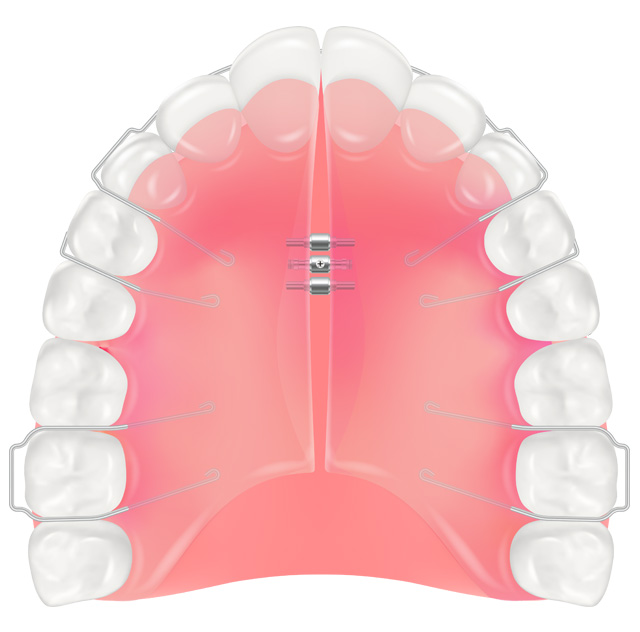

床矯正

プレート状の装置(床)を用い、装置のネジを段階的に締めることで歯列の幅を広げる方法です。歯列を広げて整えるため抜歯が不要となる可能性があり、装置は取り外し可能なので食事や歯みがきがしやすいのが特徴です。顎が成長段階の子供の矯正に適しています。